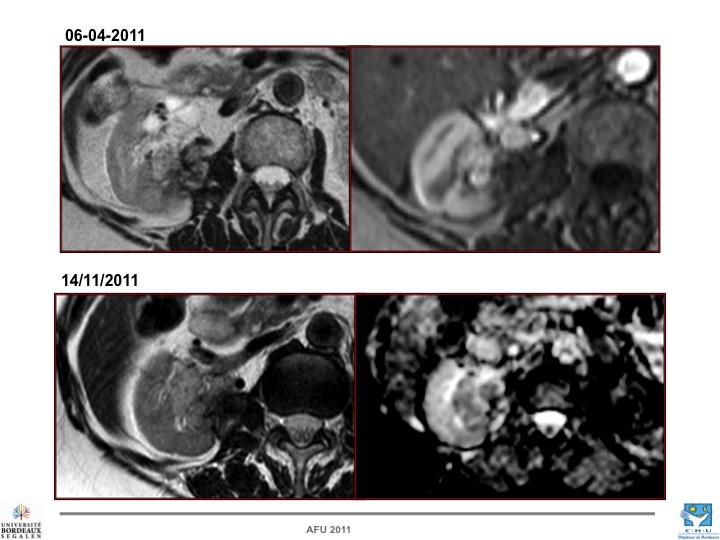

- Nos échecs

Nathalie RIOUX LECLERCQ (Rennes), Nicolas GRENIER (Bordeaux), Hervé BAUMERT (Paris)